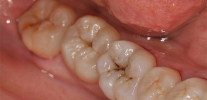

Nella foto - tipico carie delle fessure con manifestazioni esterne minime: